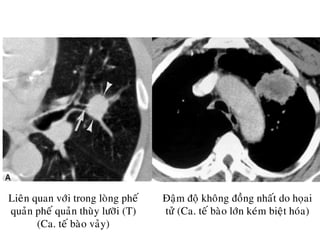

Ung thö phoåi ngoïai bieân/ Bôø khoâng

ñeàu, tuûa gai/ Co keùo maøng phoåi

Ñaäm ñoä khoâng ñoàng nhaát do hoïai

töû (Ca. teá baøo lôùn keùm bieät hoùa)

Lieân quan vôùi trong loøng pheá

quaûn pheá quaûn thuøy löôõi (T)

(Ca. teá baøo vaûy)